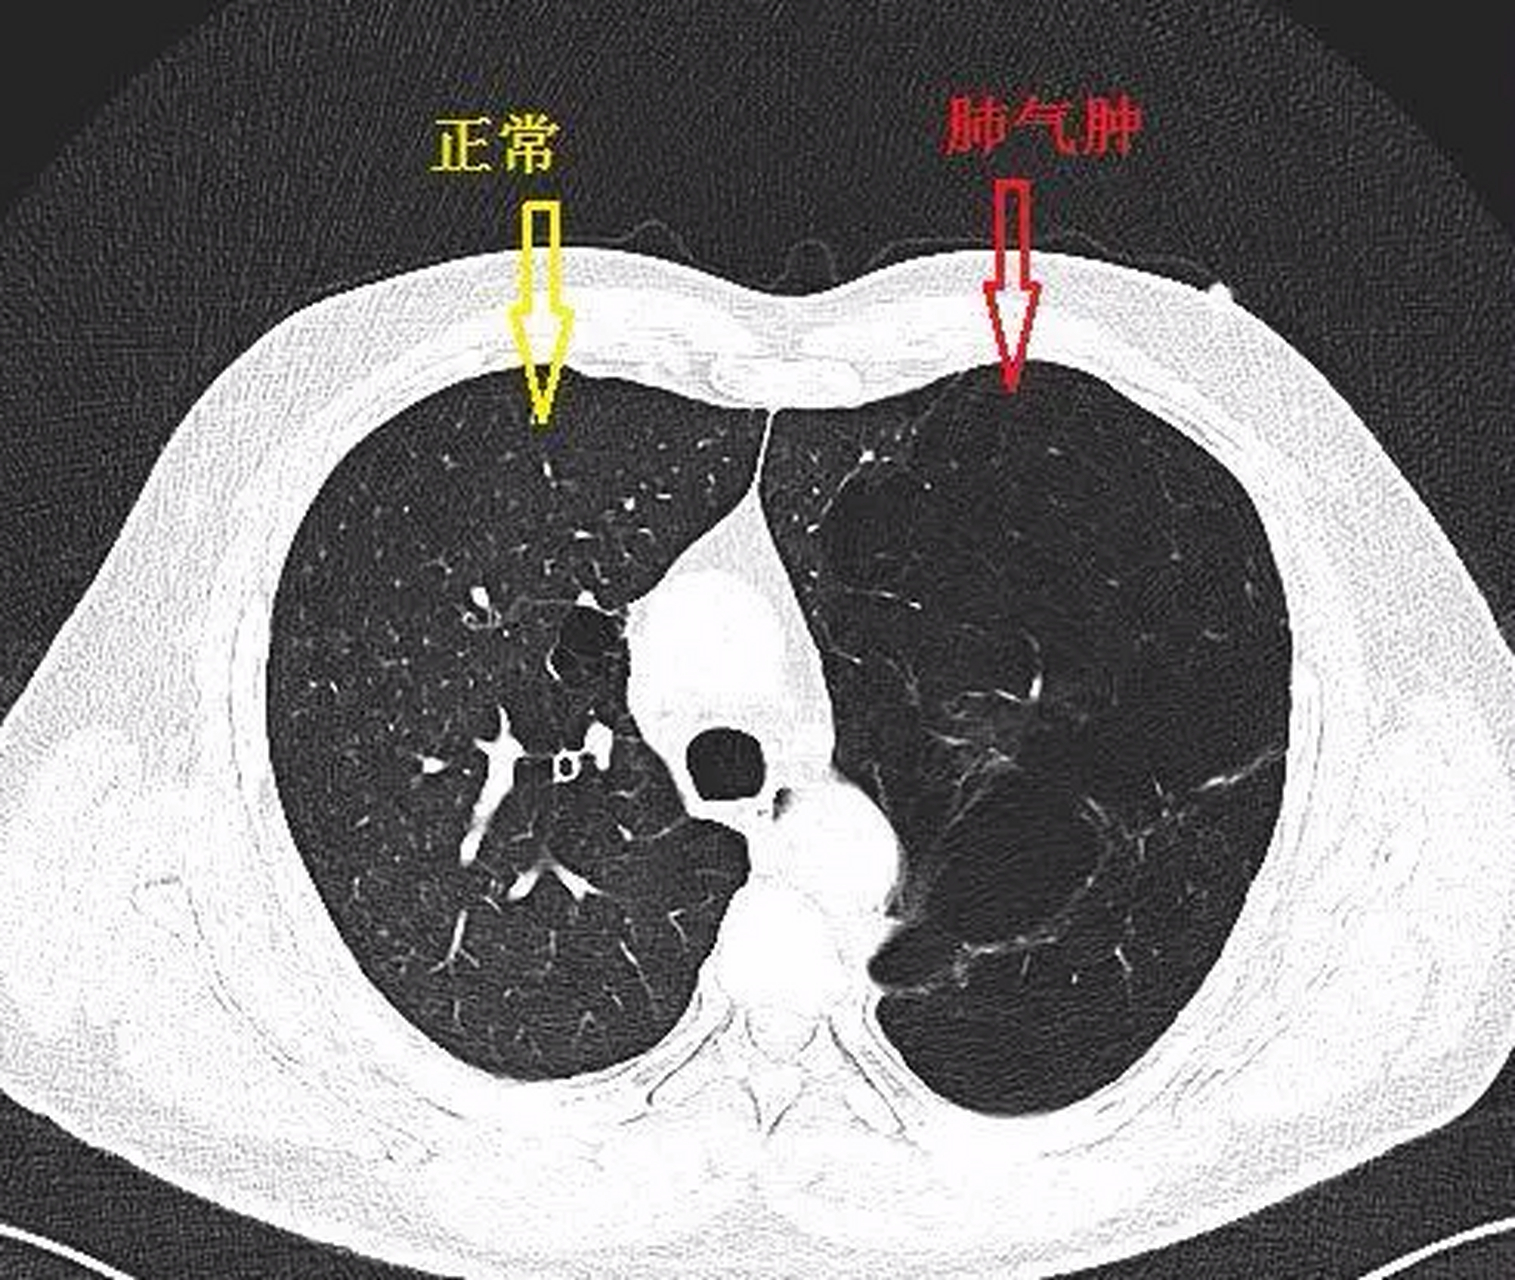

很多患者以为肺大泡就是肺气肿,其实它们在本质上是两种病症,肺大